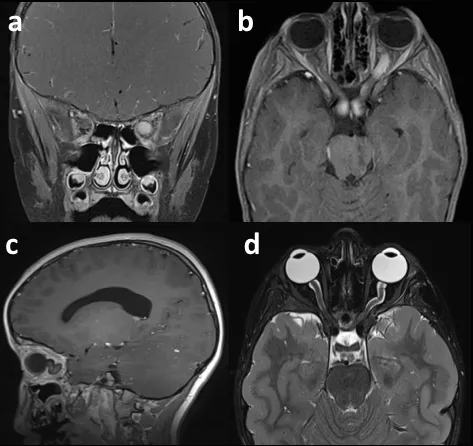

儿童颈髓胶质瘤典型表现为进行性加重的共济失调和下颅神经功能障碍。神经外科切除术在患者管理中起着重要作用,但应在配备极高精度显微神经外科手术设备并持续进行术中神经生理学监测的条件下进行,其目的是实现最大程度的安全病变切除。许多患者将需要术后化疗和/或放疗(见图2)。此外,随着时间的推移,患有此类肿瘤的儿童可能需要某种形式的枕颈稳定性手术。

图2:一名7岁儿童浸润性颈髓肿瘤的矢状位增强T1加权磁共振成像 (a)。活检及组织病理学诊断为低级别肿瘤,尽管使用了化疗(b)和放疗来控制肿瘤生长,但肿瘤仍在进展。